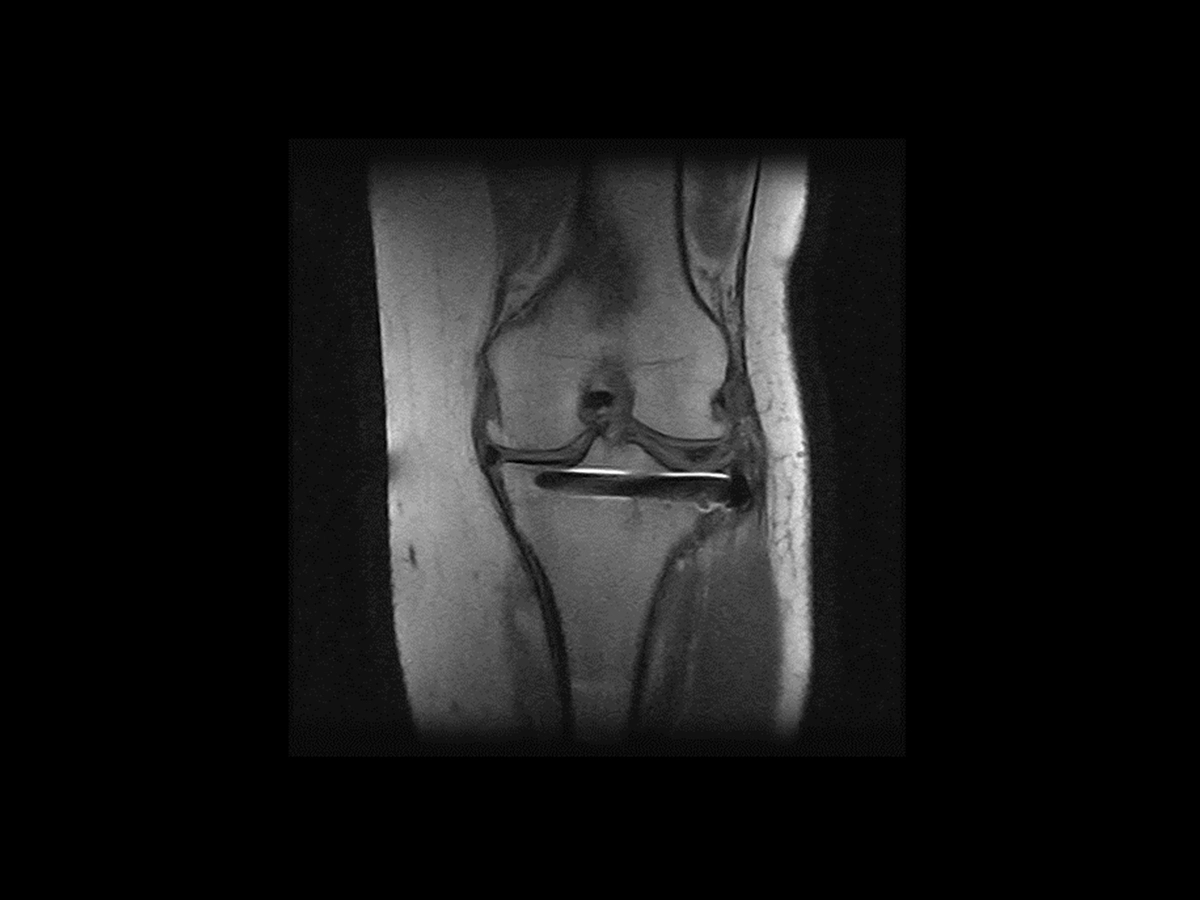

Metal Artifact Reduction

The value for a sports medicine clinician is highlighted by the capability to screen individuals with metal implants using MRI. As the patient population with metal implants continues to rise, with an estimated 2.4% of the U.S. population having hip or knee implants (Mayo Clinic, 2014), MAR becomes crucial. MAR uses an advanced gradients management system to effectively suppress or reduce in-plane metal distortions, ensuring optimal image quality. This innovation is particularly advantageous for post-operative patients, enhancing the imaging process and contributing to improved diagnostic precision in sports medicine.